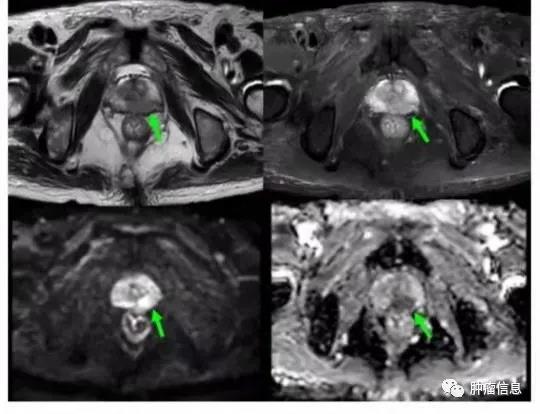

左侧外周带前列腺癌